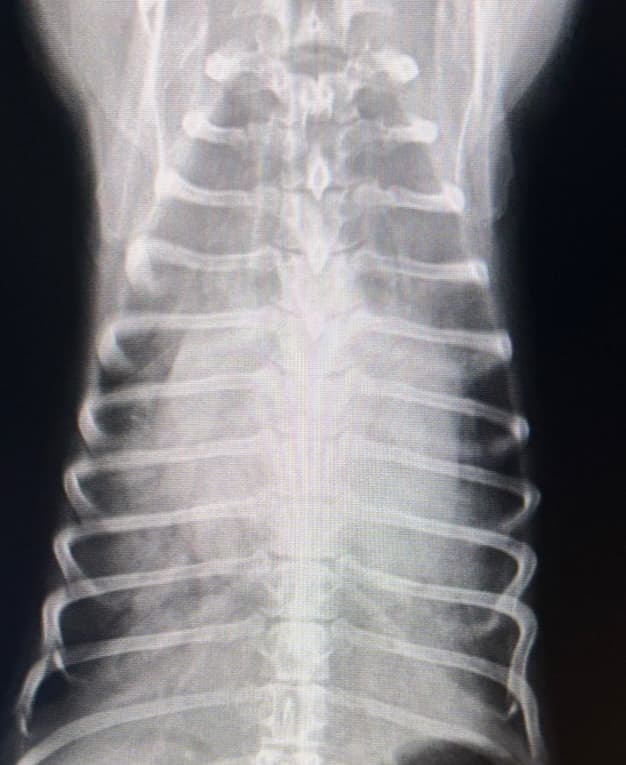

変形性脊椎症(2025/12/08)

変形性脊椎症は、身体を支えている背骨(脊椎)が年齢とともに少しずつ変形してしまう病気です。多くは無症状なためレントゲン検査で偶然見つかることも珍しくありません。しかし、変形した脊椎が神経を圧迫することで痛みや歩行異常が現れることがあります。椎間板の変性や加齢による椎体間の不安定性が原因と考えられています。症状が見られる場合は、鎮痛剤で痛みを和らげたり、温熱療法などの理学療法で筋肉の緊張をほぐしながら経過を見ていきます。最近活動量が減ってきた、歩きにくそうにしている、などの変化は病気のサインかもしれません。なにか気になる症状があればお気軽にご相談下さい。

犬の変形性脊椎症(2024/12/07)

変形性脊椎症とは身体の構造を支えている脊椎に変形が起こってしまう病気です。多くは無症状で健康診断などで偶発的に発見される事があります。しかし変形した脊椎が神経を圧迫する事でまれに痛みや運動障害を引き起こす事があります。治療は症状がある場合は鎮痛剤の投与や、温熱治療などの理学療法を行って痛みを緩和していきます。また肥満の場合には脊椎に過度な負荷をかけてしまうため、適切な体重管理が重要となります。お家のわんちゃんが高齢になって活動性が落ちてきた、歩きにくそうにしているなど気になる症状がありましたら、お気軽にご相談ください。